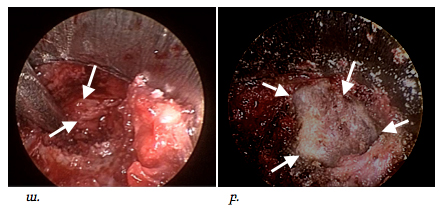

Կատարված գործողություններից հետո հայտնաբերվում էր ողի աղեղը, այն շերտազատվում էր փափուկ հյուսվածքներից աքցանների և էլեկտրոկոագուլիացիայի օգնությամբ, որից հետո բարձր արագության պնևմատիկ շաղափիչի օգնությամբ շաղափվում էր ողի աղեղի մի մասը: Եթե հիվանդի մոտ առկա էր նաև ֆորամինալ ստենոզ, պայմանավորված ելունային հոդի գերաճով, ապա վերջինս հեռացվում էր (pars superior articularis), ինչը պատկերված է նկար 4-ում:

Նկ. 4 Ներվիրահատական էնդոսկոպիկ նկար

ա. Փափուկ հյուսվածքներից շերտազատված ելունային հոդ

բ. Ողի աղեղի շաղափման փուլ

Ոսկրային պատուհան ձևավորելուց հետո նրա շրջագիծը լայնացվում էր ոսկրակրծիչների օգնությամբ մոտ 1.5-2.0սմ /փաստացի կատարվում էր էնդոսկոպիկ հսկողությամբ հեմիլամինէկտոմիա/: Այս գործողությունների ընթացքումպահպանվում էր դեղին կապանի ամբողջականությունը, ինչըայս փուլի ժամանակ կրում էրպաշտպանիչ ֆունկցիա՝ կանխարգելելով կարծրենու հնարավոր վնասումըշաղափով կամ ոսկրակրծիչներով: Ոսկրային պատուհանի ձևավորումը ցույց է տրված նկար 5-ում:

Նկ. 5 Էնդոսկոպիկ հսկողությամբ ոսկրային պատուհանի ձևավորման փուլ

ա. մասնակի ոսկրային դեֆեկտը շաղափելուց հետո (ցույց է տրված սլաքով)

բ. Ձևավորված ոսկրային պատուհան, միևնույն ժամանակ պահպանված է դեղին կապանի ամբողջականությունը (ցույց է տրված սլաքով)

Հաջորդ փուլը համարվում էր վիրահատության ամենակարևորը: Այս ժամանակ կատարվում էր դեղին կապանի շերտազատում կարծրենուց: Վերջինս կատարվում էր գնդիկաձև ծայր ունեցող կեռիկի օգնությամբ: Այս գործողությունների ժամանակ կարևոր էր խուսափել կարծրենու վնասումից կամ էլ էպիդուրալ երակային ցանցի վնասումից, որի արյունահոսությունը դժվարությամբ էր ենթարկվում կանգնեցման: Սկզբից բացազատվում էր կարծրենին մեդիալ ուղղությամբ՝ հասնելով միջին գիծ, որից հետո հետադարձ գործողություններով բացազատվում էր ողնաշարային խողովակի լատերալ սահմանը, հայտնաբերվում էր նյարդարմատը և վերջինս շերտազատվում էր կոմպրեսիա առաջացնող հյուսվածքներից մոտ 1.5սմ երկարությամբ, ինչը պատկերված է նկար 6-ում:

Նկ. 6 Կարծրենու շերտազատման փուլ

ա. Կարծրենին բացազատված է մեդիալ ուղղությամբ (ցույց է տրված սլաքով)

բ. Բացազատված է ճնշված նյարդարմատիկը (ցույց է տրված սլաքով)